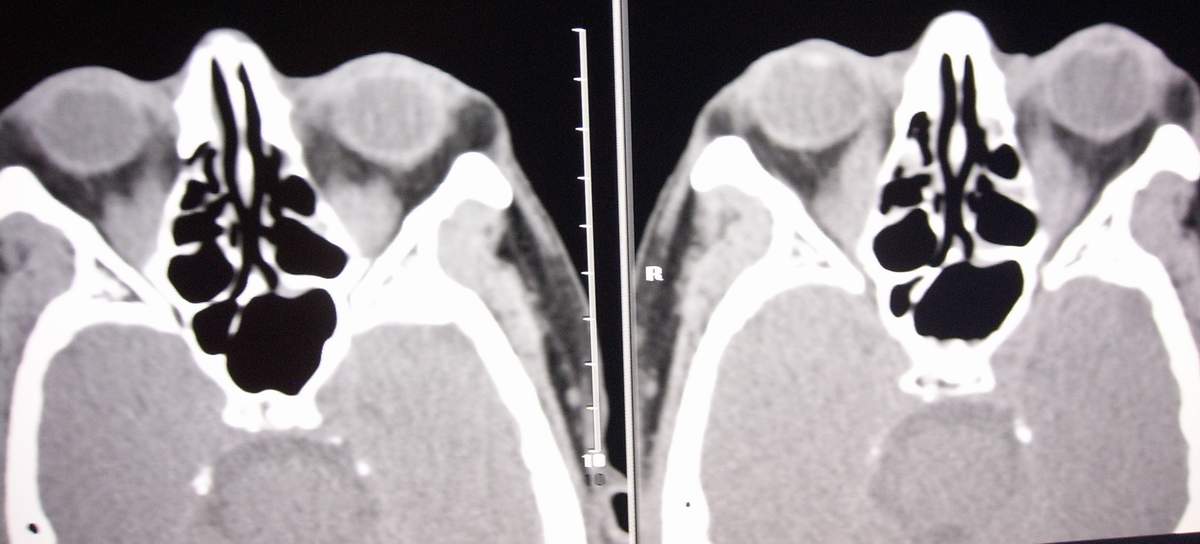

男,59岁。

双眼内直肌增粗,病人是否有甲抗病史。

从轴位图象上看,主要是双侧内直肌增粗,但在冠状位可见双侧多条眼外肌均有增粗,尤以内、下、上直肌显著,肌肉间隙分界清楚。graves病眼眶改变应首先考虑,请结合甲状腺相关检查。

考虑格氏眼病,常为对称性发病,下直肌和内直肌最常受累,如无甲亢则为眼型格氏病,炎性假瘤肌腱与肌腹都肿大,且眼肌附着处眼环增厚,模糊。

为什么没有病史啊?双侧内直肌对称性增粗,以肌腹部为主,首先考虑graves病。炎性假瘤不除外。

另格氏眼病与炎性假瘤鉴别点:主要以球后脂肪间隙的清晰度来衡量。本例,球后脂肪间隙清楚,应更支持格氏眼病。